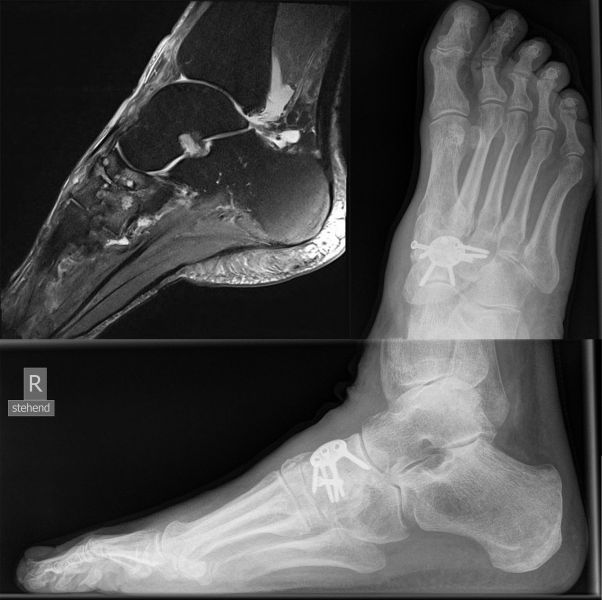

Talonavikular-, navikulocuneiforme- und calcaneocuboidale Arthrosen, also Arthrosen in der Chopart- und Bona-Jäger-Gelenklinie, zeigen sich wesentlich seltener und können in Kombination von Arthrosen aller Gelenke des Mittelfußes auftreten. Die Diagnostik beinhaltet grundsätzlich die ausführliche Untersuchung des gesamten Fußes im Stehen, im Liegen und beim Gehen. Ein Röntgenbild des Fußes im Stehen in zwei Ebenen, ergänzend eine schräge Aufnahme, sowie Saltzman und OSG-Bildgebung sind für die Diagnose und Therapieplanung essentiell. Bei Planung eines operativen Eingriffes sollte eine Computertomographie des gesamten Fußes durchgeführt werden. Zunächst sollte die konservative Therapie mittels Schmerzmedikation, Infiltration, Manueller Therapie, Einlagen, Schuh-Modifikation, Orthesen, orthopädischem Schuhwerk und ggf. eine Strahlentherapie voll ausgeschöpft werden. In zweiter Linie steht die operative Therapie. Chirurgische Eingriffe beinhalten typischer Weise die selektiven Arthrodesen der betroffenen Mittelfußgelenke. Hier wird meist die mediale Säule behandelt, die Arthrodesen der mobileren lateralen Säule sind ein Thema in der Diskussion 2.

Die Diagnostik beinhaltet die komplette klinische Untersuchung des Patienten bei entkleidetem Unterkörper mit Funktionstests, Abtasten der entsprechenden Gelenkreihen (Chopart, Bona Jäger und Lisfranc) und Überprüfung der Beweglichkeit der Tarsometatarsalgelenke mit dem Klaviertasten-Test 11. Beurteilt werden Fußformveränderungen, osteophytäre Anbauten, sowie eine mögliche Verkürzung des M. gastrocnemius-soleus-Komplexes mit Hilfe des Silfverskjöld-Tests 12. Es werdemRöntgenaufnahmen des Fußes im Stehen in 2 Ebenen und ergänzend eine Schrägaufnahme des Fußes durchgeführt. Bei Fußfehlstellungen erfolgt zusätzlich das Röntgen des oberen Sprunggelenks im Stehen und eine Saltzman-Aufnahme 13.

Bei Nachweis von degenerativen Veränderungen ist für eine Therapie- und ggf. Operationsplanung eine Dünnschicht-Computertomografie des Bereiches notwendig. Darüber hinaus sind unter einer Röntgendurchleuchtung durchgeführte, diagnostische Infiltrationen mit einem lokalen Anästhetikum möglich, um den Ort der Beschwerden genauer differenzieren zu können.

Bei zusätzlichen Sehnenpathologien kann eine Kernspintomografie hilfreich sein. Die Durchblutung sollte ebenfalls geprüft und dokumentiert werden, ferner ein neurologischer Status erhoben werden.

Die Diagnostik beinhaltet die ausführliche körperliche Untersuchung und ein Röntgenbild des Fußes im Stehen in zwei Ebenen. Bei Planung eines operativen Eingriffes empfiehlt es sich die konventionelle Röntgendiagnostik durch eine Computertomographie, ggf. auch MRT des Areales zu ergänzen. Zunächst sollten die Möglichkeiten der konservativen Therapie ausgeschöpft werden. Bei weiterbestehendem, hohen Leidensdruck und eindeutigem Wunsch des Patienten sollte die operative Therapie geplant werden.